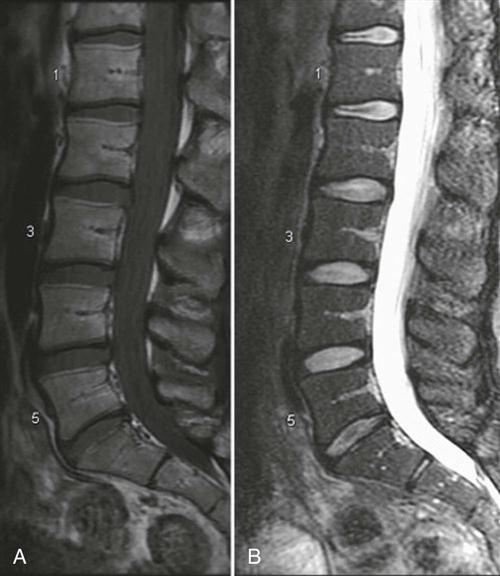

MRI is a noninvasive technique that can be used in several planes (transaxial, coronal, or sagittal) to delineate bony and soft tissues. This technique is commonly used to diagnose tumors, to view the spinal cord within the spinal canal, and to assess for syringomyelia, cord infarction, or traumatic injury.124,268 The delineation of soft tissues is much greater with MRI than with CT.269 For example, with MRI, the nucleus pulposus and the annulus fibrosis are easier to differentiate because of their different water contents, making it the preferred imaging modality for disc disease and radiculopathy (Figures 9-120 through 9-124).23,256,270,271 As with other diagnostic imaging techniques, clinical findings must support what is seen before the structural abnormalities can be considered the source of the problem.255,264,272–274 Up to 30% of asymptomatic patients with no history of low back pain show disc abnormalities.23,275 Things to look for on MRI are disc height, presence or absence of annular tears, degenerative signs, and end plate changes.23